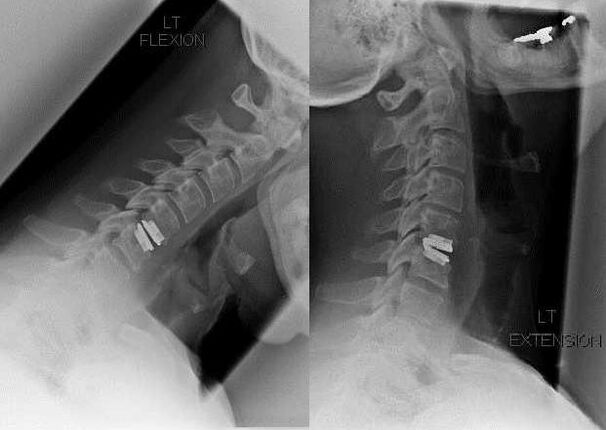

intervención quirúrgica

Las indicaciones para la intervención quirúrgica incluyen el fracaso del tratamiento conservador y las complicaciones de la osteocondrosis cervical, como la mielopatía discogénica, el síndrome de la arteria vertebral y el síndrome radicular. Para descomprimir la médula espinal, los vasos sanguíneos y las raíces de la médula espinal, se realizan los siguientes procedimientos:

- laminectomía;

- Laminotomía;

- foraminotomía;

- resección de la articulación facetaria;

- Discectomía.

Durante la cirugía, se pueden extirpar fragmentos óseos y ligamentos, y el disco se puede extirpar total o parcialmente. Para hernias pequeñas, a menudo se realiza la vaporización con láser del núcleo del disco.

Después de la resección de estructuras vertebrales, a menudo se requiere la estabilización de los segmentos de movimiento de la columna mediante fusión espinal o instalación de autoinjertos óseos y dérmicos.